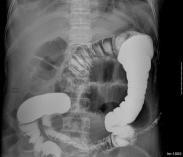

傷寒是傷寒桿菌引起的。主要的病理特征是全身網狀內皮系統的增生反應,以回腸下段淋巴組織的病變最為顯著。副傷寒,分別由副傷寒甲,乙,丙桿菌引起。它的臨床表現、診斷、治療和預防與傷寒相同。

- 常見癥狀:發熱畏寒、全身不適、厭食、腸出血、右下腹痛、有明顯腹部壓痛、血便

傷寒腸穿孔,傷寒腸穿孔癥狀,傷寒腸穿孔治療